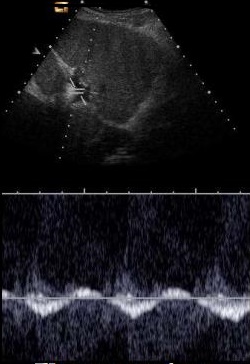

Cirrhose du foie : le flux de la veine

porte est biphasique (normalement ce

flux est monophasique ) . |

Et ce flux se diminue a

inferieure de 15cm/sec et reverse ( flux

inverse ) |